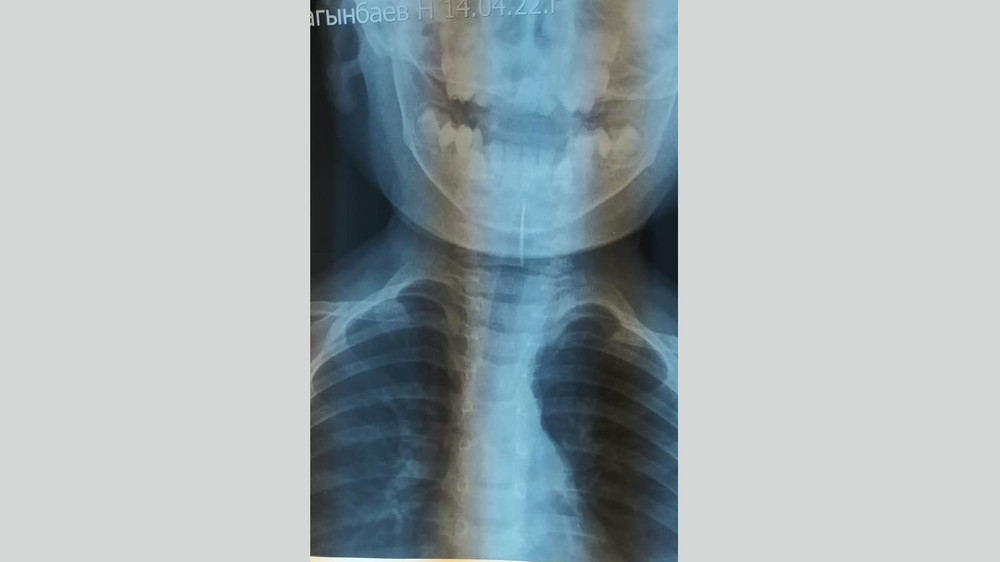

Ош шаарында бейтапканага шашылыш жеткирилген наристенин окуясы